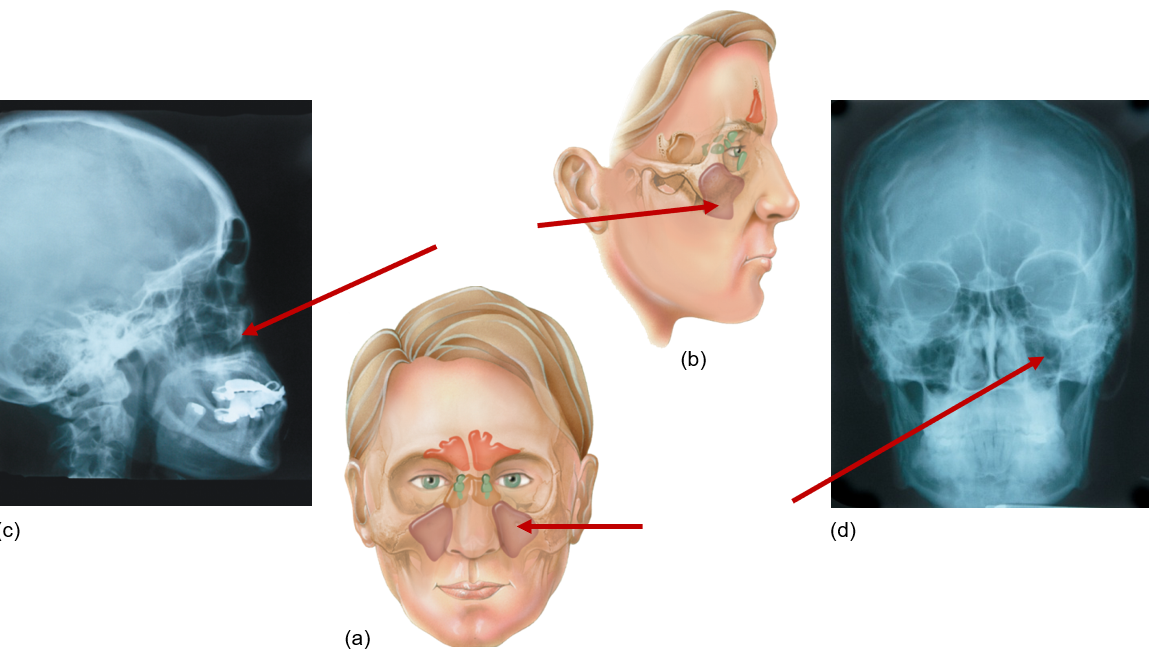

Frontal sinus

Front of head, above eyes

Sphenoid sinus

Behind eyes, near temples

Ethmoid sinus

Between eyes

Maxillary sinus

Next to nose, under eyes, maxilla